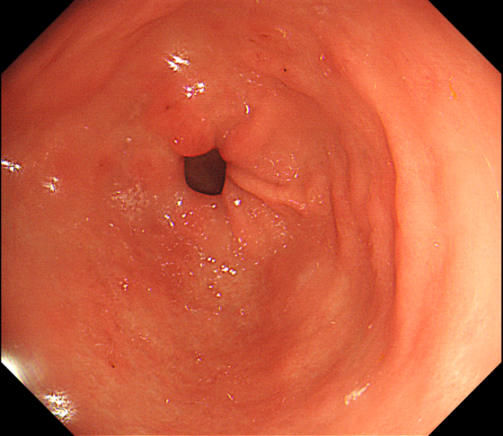

超声内镜引导下穿刺:脓液流出

于主任带领团队在超声内镜的定位下,穿刺针避开大血管,精准刺入胃脓肿腔内,抽出脓液约0.5ml;并留置引流管持续引流。术后王女士腹痛等症状马上缓解。回家口服消炎药一周后来院复查,胃镜显示手术部位恢复正常。